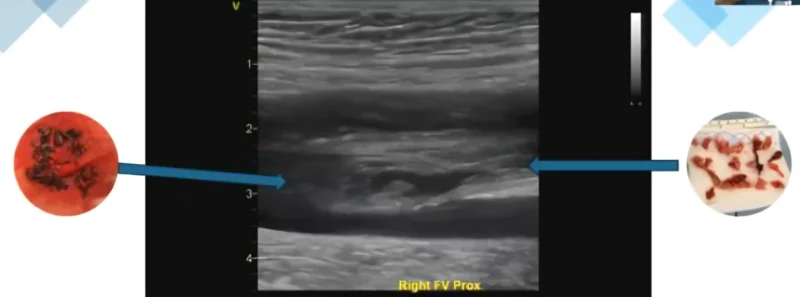

”Spot the Clot. Stop the Clot

In honor of Blood Clot Awareness Month, we are bringing clinicians together to improve how we detect and treat venous thromboembolism (VTE).

This B-mode ultrasound image shows thrombus within the femoral vein, visible as echogenic material within the vessel lumen. Early venous thrombi are fibrin-rich structures made up of platelets, red blood cells, and inflammatory components.

Research has demonstrated that ‘clot begets clot,’ meaning an existing thrombus can continue to propagate through ongoing fibrin deposition and platelet aggregation. Within 5–7 days, thrombi begin to organize as fibroblasts and collagen deposition transforms the clot, making it more structured and increasingly resistant to thrombolysis.

Understanding how clot composition evolves and how it appears on ultrasound is critical for clinicians aiming to accurately detect, interpret, and manage venous thromboembolism (VTE).